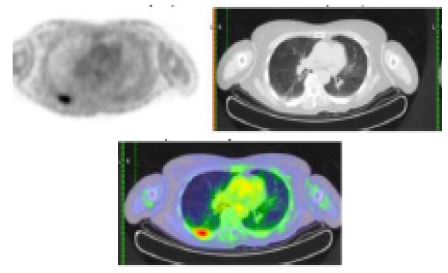

A Positron Emission Tomography (PET) CT was also performed for staging and further work-up, showing the following hypermetabolic lesions: enlarged pre-vascular lymph node, diffuse enhancing gastric wall thickening, enlarged perigastric lymph nodes, lobulated enhancing left pelvic side wall mass with erosive changes in the adjacent left ischium and acetabulum, enlarged left external and internal iliac lymph nodes and enlarged lymph node between the left pectineus and adductor muscles (Figure 5).

Figure 5: PET CT scan showing hypermetabolic lesions.

During the fourth month follow-up, no recurrence of the hyper metabolic lesions was observed as seen on the repeat PET CT scan (Figure 6) showing complete metabolic response with no hyper metabolic nodal disease and interval disappearance of the enlarged lymph nodes/mass in the chest, abdomen and pelvis. There was interval resolution of the diffuse enhancing gastric wall thickening showing good treatment response. Until present, our patient is in complete remission.

Image is Not Display Check it

Figure 6: PET CT scan showing complete metabolic response with no hyper metabolic nodal disease and interval disappearance of the enlarged lymph nodes/mass in the chest, abdomen and pelvis.

Whole-body FDG PET/CT (11/28/22)

- Enlarged prevascular lymph node

- Diffuse enhancing gastric wall thickening

- Enlarged perigastric lymph nodes

- Lobulated enhancing left pelvic side wall mass with erosive changes in the adjacent left ischium and acetabulum

- Enlarged left external and internal iliac lymph nodes

- Enlarged lymph node between the left pectineus and adductor muscles

Whole-body FDG PET/CT (4/14/23)

Complete metabolic response with no hypermetabolic nodal disease and interval disappearance of the enlarged lymph nodes/mass in the chest, abdomen and pelvis. Interval resolution of the diffuse enhancing gastric wall thickening. Known case of high-grade B-cell Lymphoma, s/p 6 cycles chemotherapy showing good treatment response.